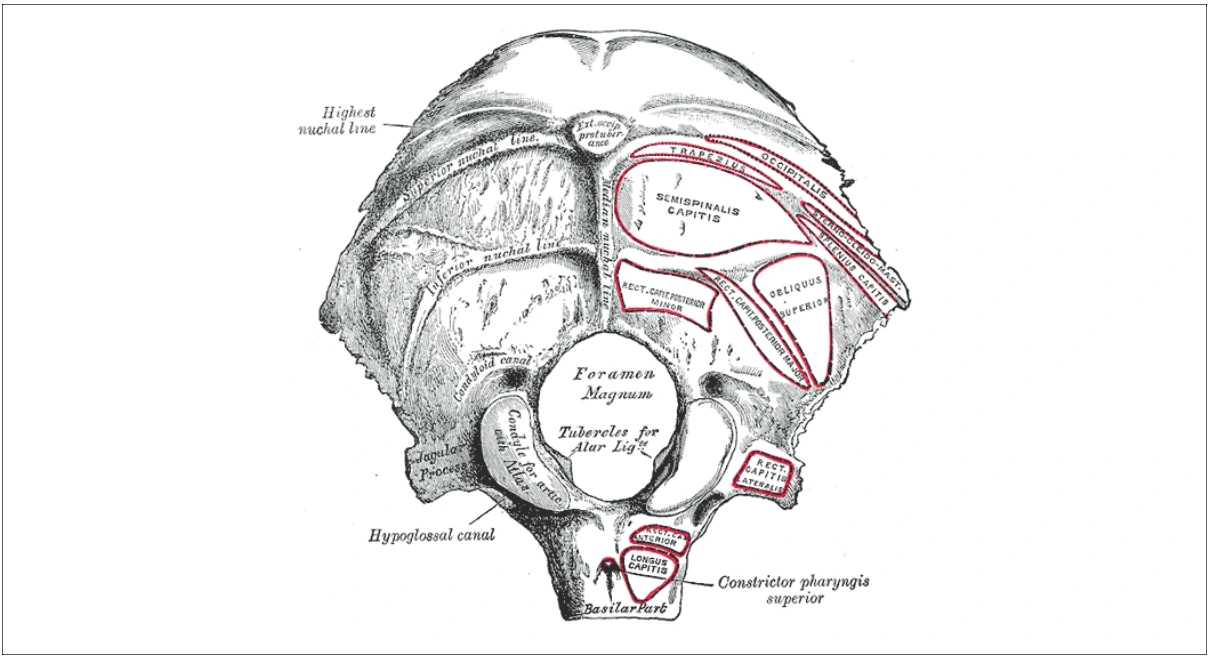

- External occipital protuberance: It is a bony prominence along the midline, situated halfway between lambda and foramen magnum.It marks the junction of head and neck, and provides attachment to nuchal ligament and trapezius muscle.

- External occipital crest: It is a ridge along the midline descending from the external occipital protuberance to the foramen magnum. It provides attachment to nuchal ligament, and also referred as median nuchal line.

- Superior nuchal lines: These are curved bony ridges extending laterally from the occipital protuberance.

- Inferior nuchal lines: These are curved bony ridges passing laterally from the middle of external occipital crest.

- Highest/Supreme nuchal lines: These are faint bony ridges seen in some cases, about 1 cm above the superior nuchal lines.

Source: Henry Gray (1918) Anatomy of the Human Body

- Occipital condyles: These are kidney-shaped bony prominences that connects the skull and vertebral column. They articulate with the first cervical vertebrae (atlas), forming the atlanto-occipital joint.

- Jugular process: It is a quadrilateral plate of bone that projects laterally from the posterior half of the occipital condyle. Its inferior surface is rough and provides attachment surface to muscles, while the superior surface bears a deep groove which is continuous with the jugular notch.

- Jugular notch: It is present on the anterior margin of jugular process. It forms the jugular foramen with similar notch present on the petrous temporal bone.

- Pharyngeal tubercle: It is a bony bump, found in the median plane, about 1 cm in front of the foramen magnum. It acts as the attachment point for the pharyngeal raphe, to which all the pharyngeal constrictor muscles are connected.